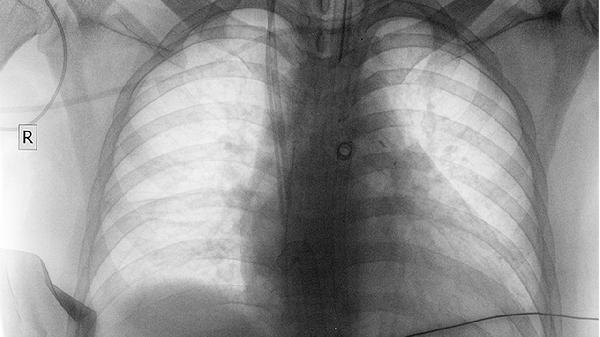

肺癌细胞转移至胸膜时,会刺激神经引发肩部牵涉痛。特点是夜间加重,普通止痛药无效,常伴随咳嗽、消瘦等症状。

根据疼痛特点选择X光、B超、核磁或肿瘤标志物筛查,不要盲目拒绝医生建议的检查项目。